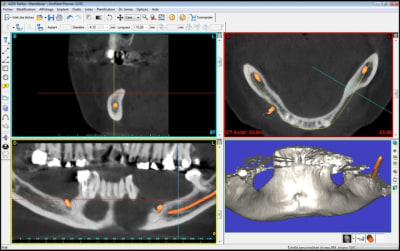

coupe_secteur_3_akuiru.jpg